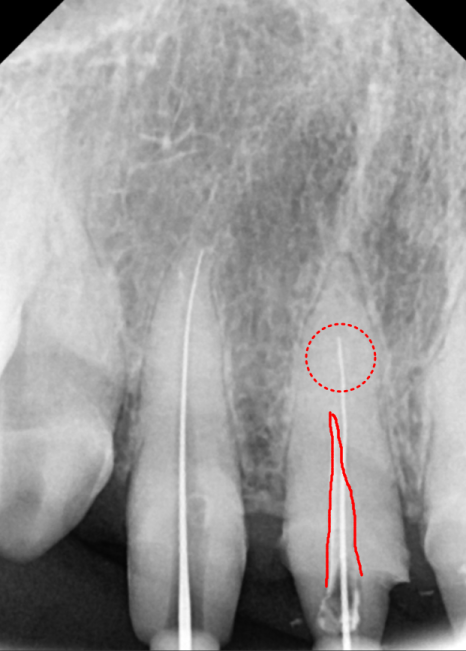

230424

이번 환자분 역시 신경이

뿌리 끝까지 제거되지 않은 상태였지만,

다행히 숨은 길을 잘 찾아내어

3번의 꼼꼼한 소독 끝에

안전하게 치료를 마무리할 수 있었습니다.

230426